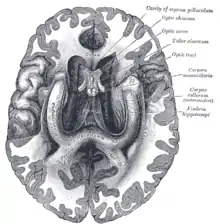

Соскоподібні тіла (corpora mamillaria)

Соскоподібні тіла на коронарному зрізі мозку через внутрішню область третього шлуночка (corpora mamillaria)